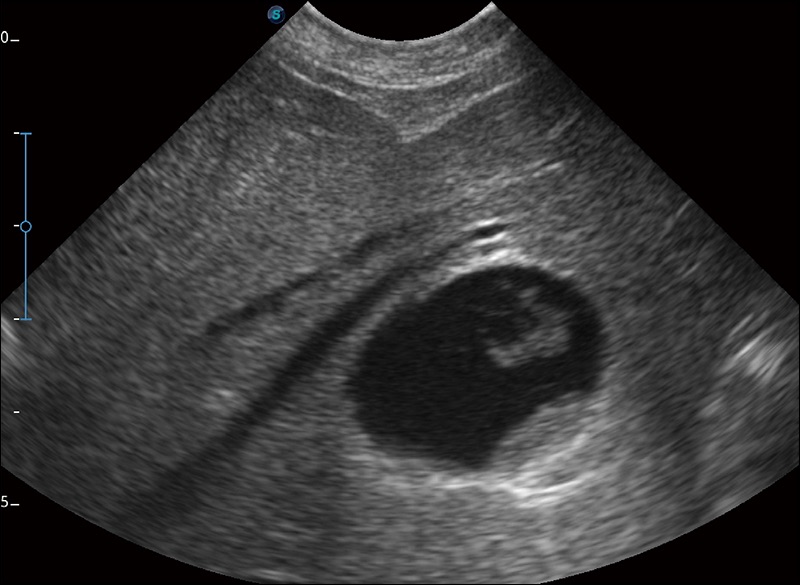

实时宽景成像

可实时观察感兴趣区域和病变位置